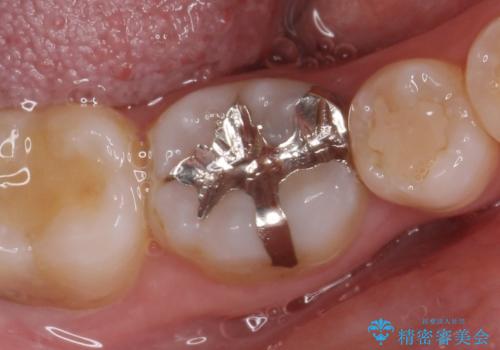

- 銀歯を白くして欲しいといらっしゃった方の症例です。

銀歯及び虫歯を除去後、セラミックインレーによる修復を行いました。